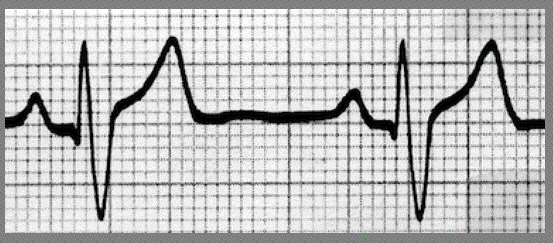

When counting small boxes always remember there are 5 small boxes going across for each large box. Rhythm must be regular. Remember, each small box is .04 seconds Count from the Tip of the R wave to the Tip of the next R wave. In EKG we count 1/2 boxes too. In the example above I am counting 26.5 small boxes. Let's calculate the R wave to R wave heart rate.

26.5 x .04 = 1.06 seconds: 60/1.06 = 57 b/min. Heart rate is 57 beats per minute (b/min)